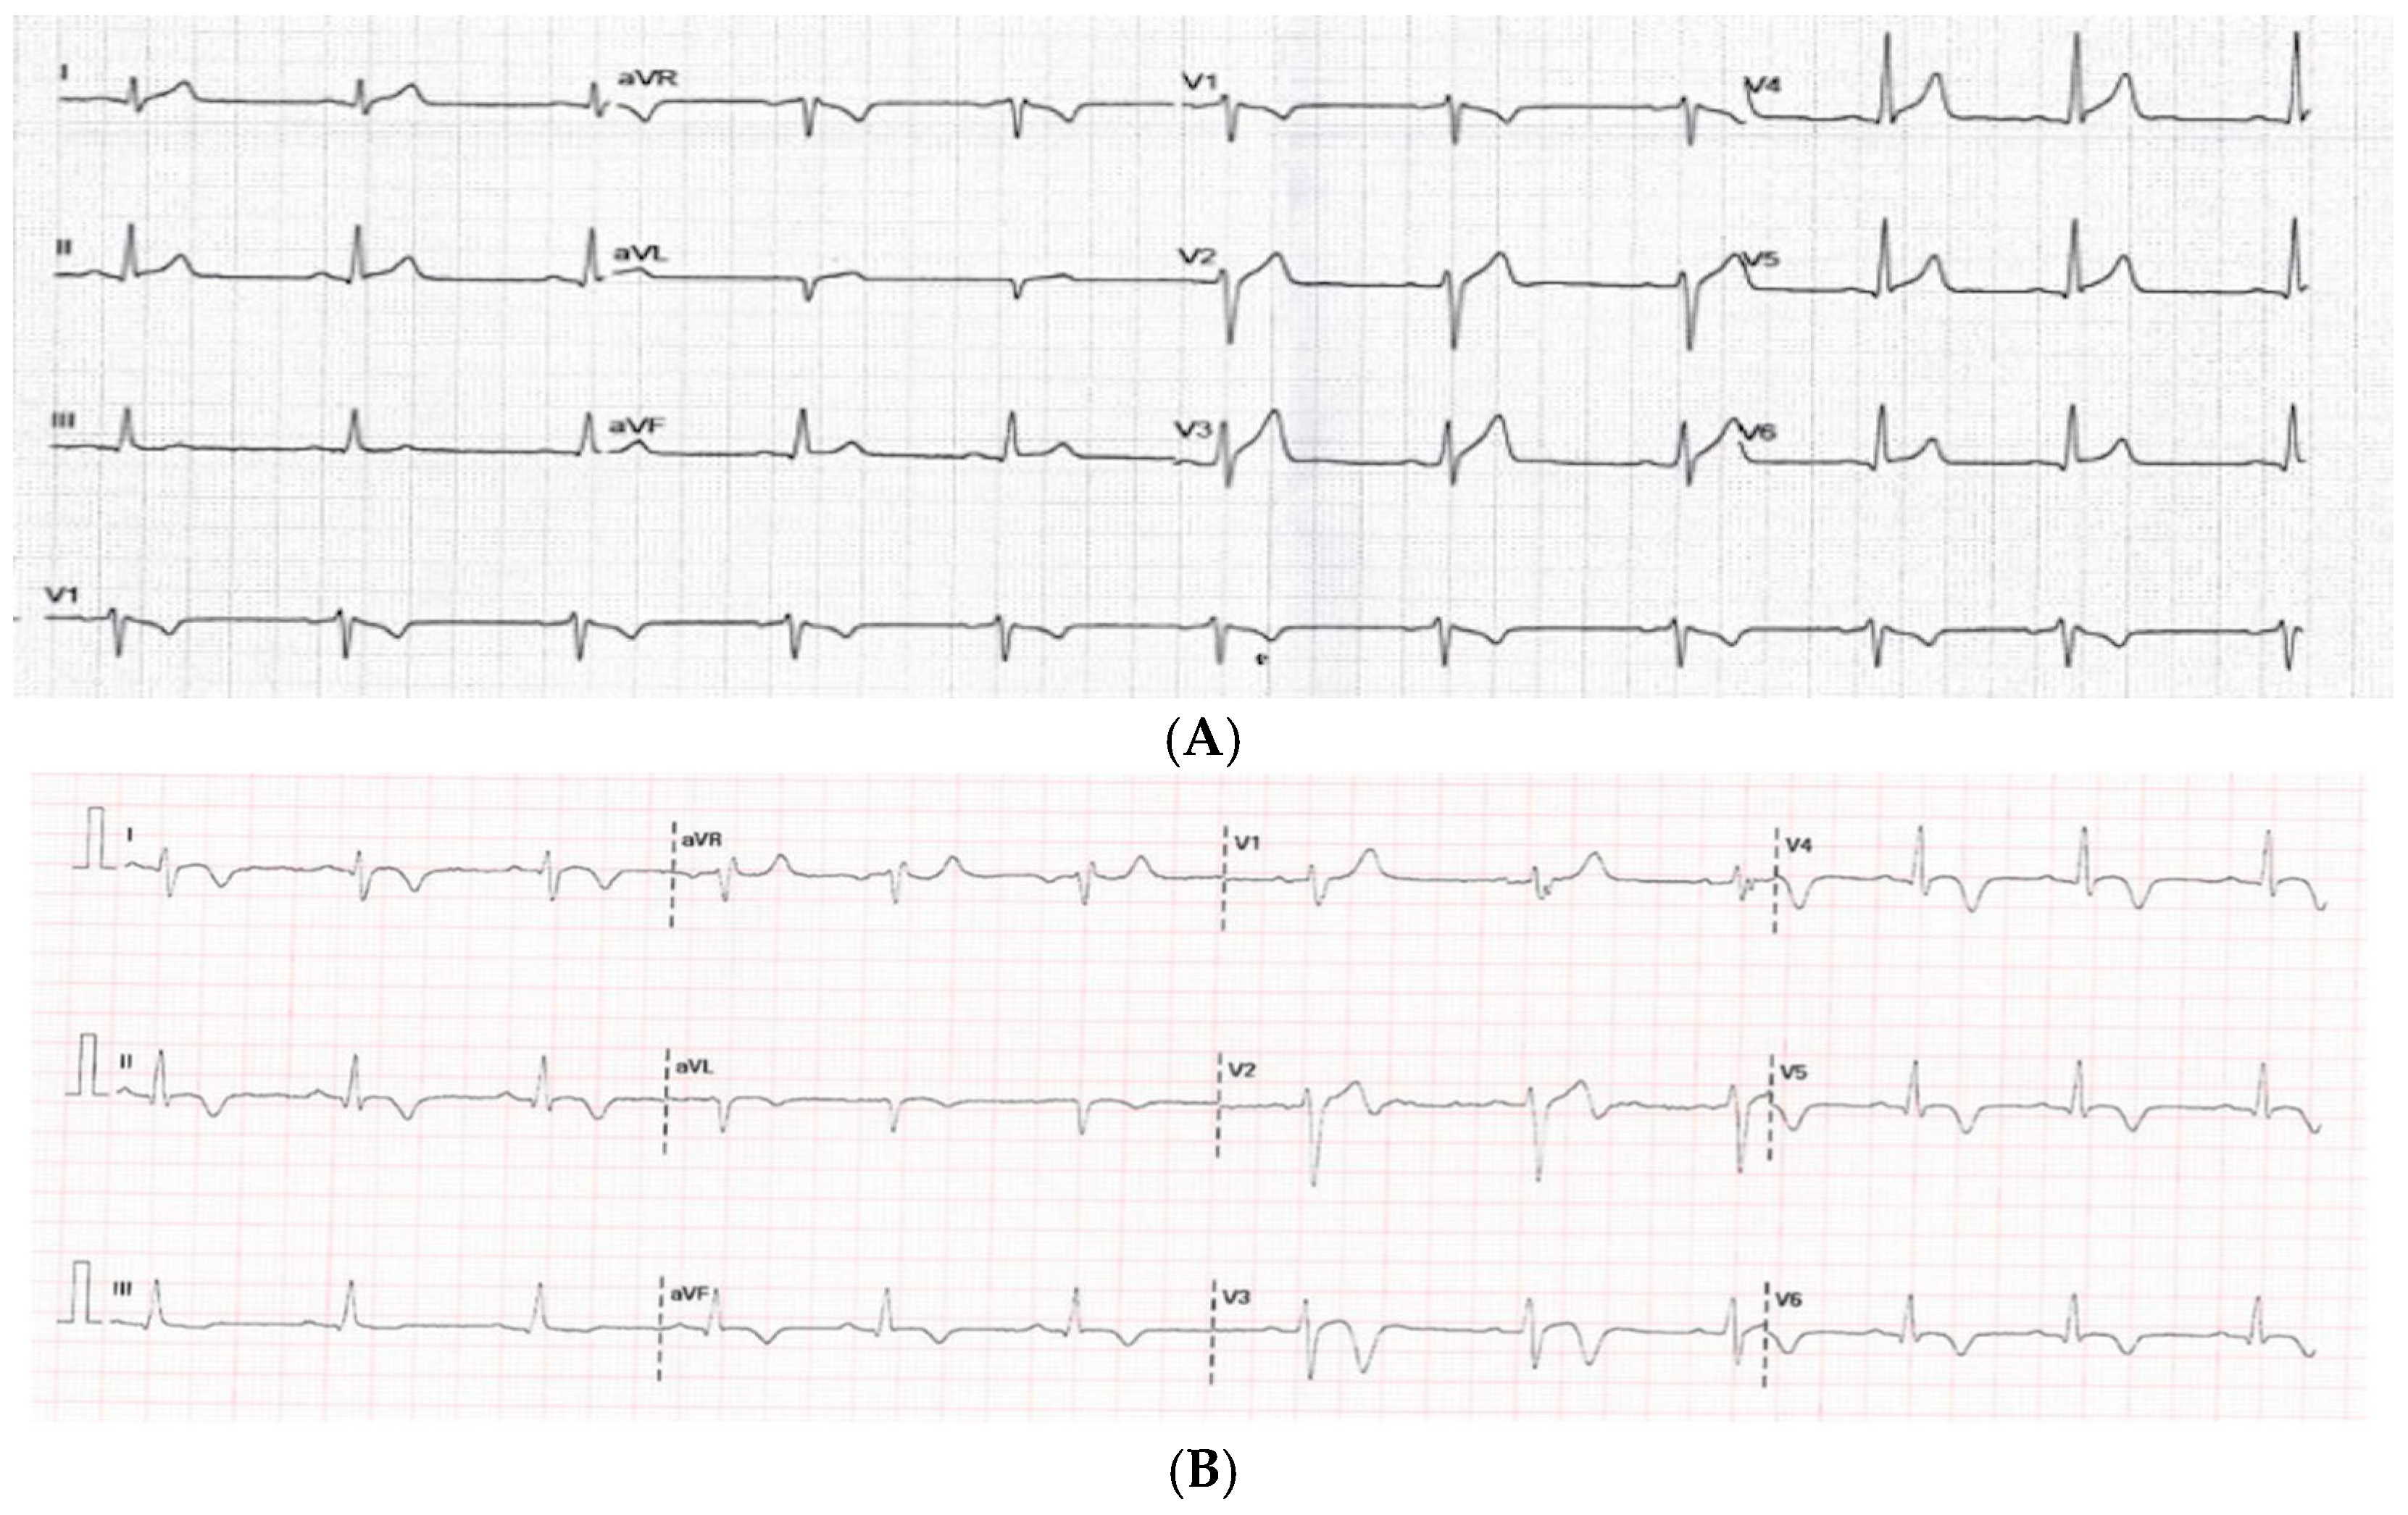

3.3.1. Electrocardiogram

3.3.4. Comparison Based on ECG Findings on Admission